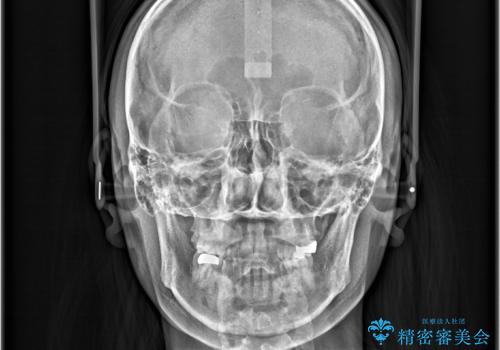

- すきっ歯と切端咬合(上下の前歯が先端で当たるかみ合わせ)を主訴にご来院された患者様です。

矯正検査を行った結果、非抜歯でインビザラインによる治療が可能と判断し、マウスピース矯正で改善を行いました。

11ヵ月で矯正治療が終了し、前歯の隙間も改善、見た目とかみ合わせも良好な状態となり、患者様にも大変ご満足いただけました。